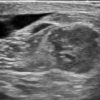

Ung thư vú

» Thông tin: Nữ giới – 69 tuổi.

» Lâm sàng: Kiểm tra sức khỏe.